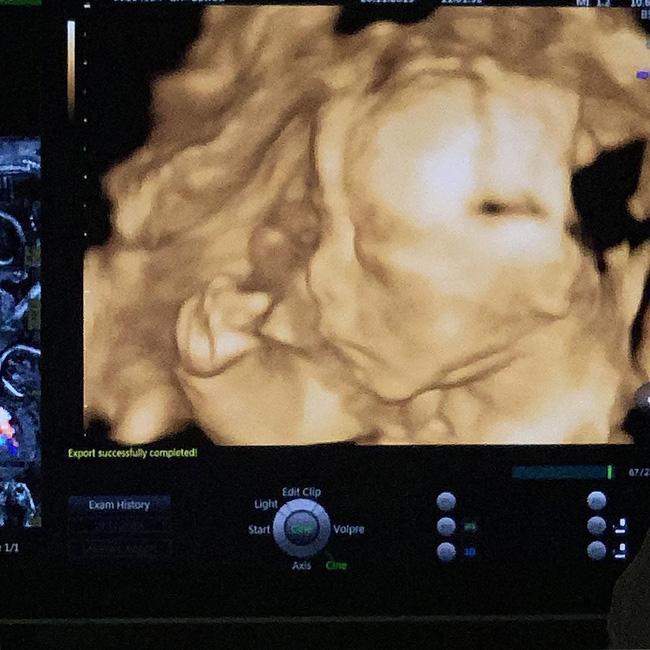

Hình ảnh siêu âm cháu trai Minh Nhựa.

Kể từ khi thông báo lên chức, Joyce Phạm thường xuyên khoe hình ảnh bầu bí và niềm vui được làm mẹ trên mạng xã hội. Mới đây, cô tiếp tục gây chú ý khi khoe hình ảnh siêu âm thai nhi. Từ chia sẻ cho thấy, đang trong giai đoạn phát triển nhưng cháu ngoại Minh Nhựa đã có chiếc mũi cao.

Kèm theo hình ảnh Joyce Phạm chia sẻ, ban đầu hai vợ chồng dự định đặt tên con ở nhà là Bơ nhưng giờ sẽ đổi thành Tít vì bà ngoại thích như vậy.